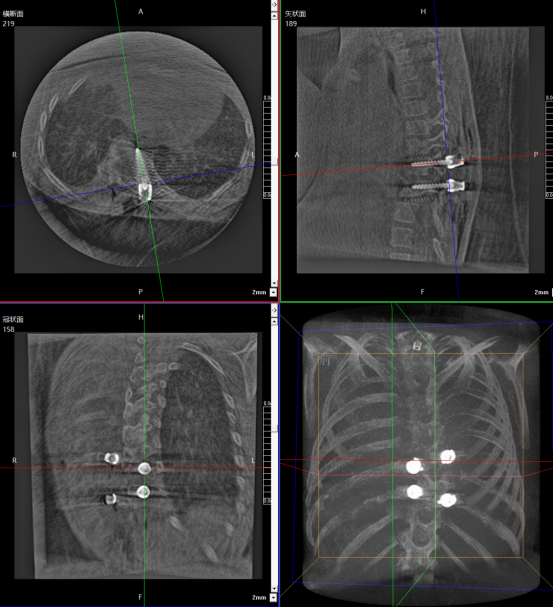

Age: 10 years

Gender: Female

Procedure: Spinal revision surgery

The patient initially underwent fixation with growing rods. However, due to rapid growth, the original fixation system could no longer accommodate her growth. A revision surgery was therefore required to adjust the fixation device and re-correct the spinal deformity.

Preoperative imaging of the pediatric patient

Pediatric spinal revision surgery is far more complex than primary surgery. The core challenges lie in anatomical adhesions and limited surgical visibility. The initial operation oftentends to induce scar tissue formation around the spinal column, which adheres muscles, blood vessels, and nerves to adhere to the spine and internal fixation devices, significantly increasing surgical difficulty. At the same time, scar-induced visual obstruction blurs the surgical field and impairs the surgeon’s ability to accurately identify spinal segments.

Children’s bones are softer than those of adults, and the initial surgery may have already caused some degree of bone damage. During revision procedures, this further increases the difficulty of implanting internal fixation devices. Improper screw depth or angulation can easily lead to implant loosening and compromise surgical outcomes

The combination of three-dimensional imaging and a surgical robot effectively addresses the critical challenges of complex anatomy and the need for high-precision localization. This synergy enables visualized preoperative planning, sub-millimeter intraoperative positioning accuracy, and a significant reduction in surgical risks.

The 3D C-arm performs image acquisition and 3D reconstruction.

Robot-assisted screw insertion path planning

Robot-assisted precise precise screw placement.